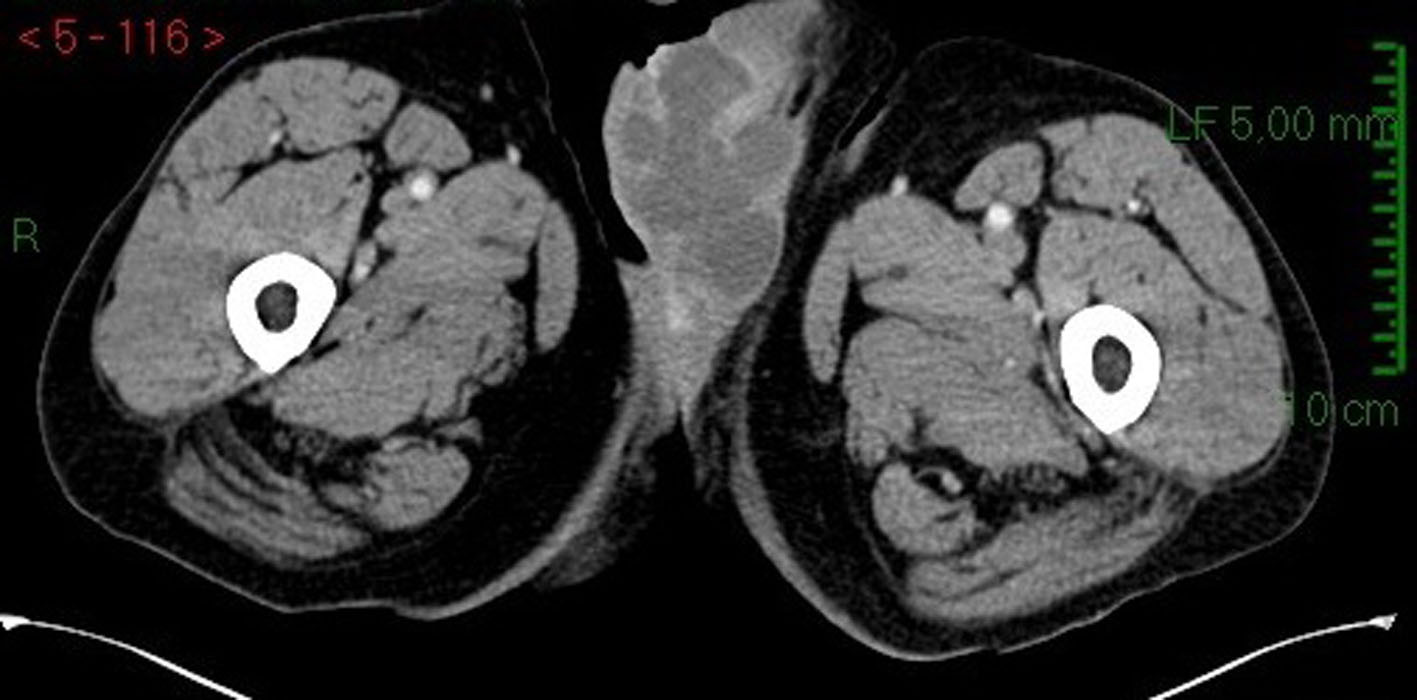

We admitted an 81-year-old man to our hospital for fever and a scrotal ulcerative lesion with clear signs of infection. His past medical history included bilateral cryptorchidism surgically treated in young age, inguinal hernia and hypertension. Scrotal examination showed an indolent malodorous scrotal ulcer, discharging abundant purulent and mucinous fluid. We performed a bacterial swab and cold biopsy and started empirical antibiotic therapy. After a few days, fever disappeared and white blood cells dropped within normal range. Bacterial swab was positive for Citrobacter farmeri and Staphylococcus saprophyticus, therefore, we started a targeted antibiotic therapy. Biopsy showed atypical cells, macrophages, bacteria and mucin. Abdomen/pelvis CT scan (Fig. 1) revealed a massive left inguinal hernia containing fat and bowel and a small contralateral inguinal hernia containing only adipose tissue. CT showed a large perineal and scrotal area with multicystic aspects and air microbubbles, as a result of an abscess (Fig. 2, 3); no intraperitoneal or retroperitoneal fluid was observed.

![]() Click for large image | Figure 2. CT scan image: transversal section of scrotal area in arterial phase. |